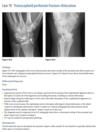

Anteroposterior (Fig. 2.16.1) and lateral

(Fig. 2.16.2) radiographs of the left knee show a semi-

circular lucency, with an adjacent bony fragment,

on the lateral aspect of the medial femoral condyle

(arrows).

sagittal T2-weighted MR

image in the same patient demonstrates minimal

linear increased signal intensity in the same region

as the lucency, located between the subchondral

bone and the fragment (Fig. 2.16.3, arrow). The frag-

ment has low signal intensity and is not completely

covered by cartilage.

Osteochondritis dissecans (osteochon-

drosis) of the medial femoral condyle

from an osteochondral fracture

that was initially caused by shearing, rotatory, or

tangentially aligned impaction forces.

The presence of linear high T2-weighted

signal intensity between the fragment and donor site

indicates fluid or granulation tissue and strongly sug-

gests instability of the fragment (i.e., loose in situ

fragment) (Fig. 2.16.4, arrowheads). Focal cystic areas

beneath the fragment or denudation of articular carti-

lage are also MR signs suggesting an unstable fragment.

All patients with radiographic evidence of osteochon-

dritis dissecans could potentially benefit from MRI to

assess the integrity of the donor fragments before any

surgical or arthroscopic intervention or therapy (71).